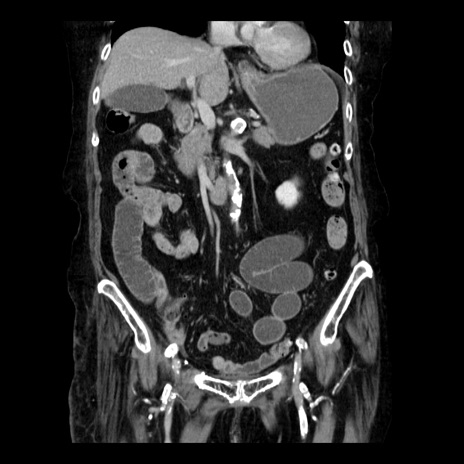

症例14(冠状断像)

【症例】 90歳代女性

【主訴】 腹痛・嘔吐

【現病歴】今朝から左側腹部痛を認めた。 経過観察していたが、嘔吐を認めたため来院。

【既往歴】 子宮癌術後

【身体所見】 意識清明、BP 127/54mmHg、P 98bpm Sp02 95%(RA)、BT 35.8°C、腹部平坦・軟腸ぜん動音聴取良好、右下腹部圧痛(+) 反跳痛なし

【データ】WBC 9800、CRP 0.46